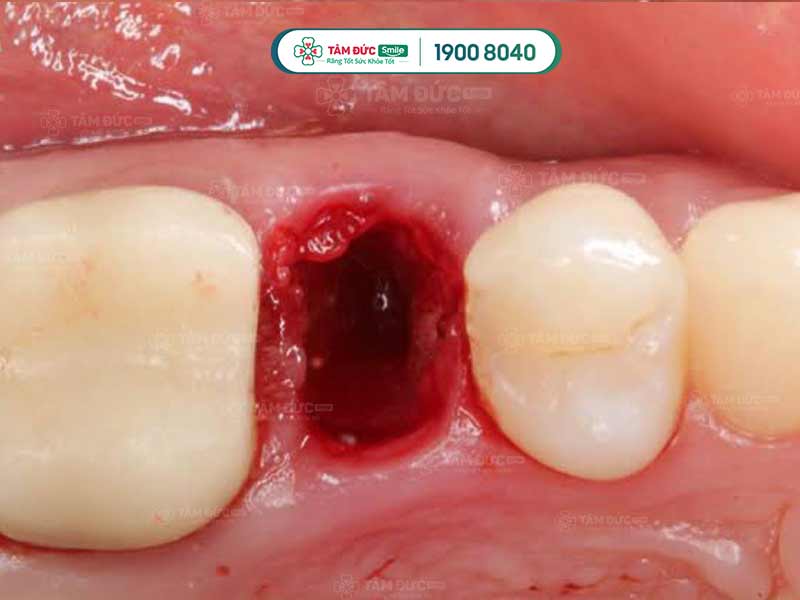

Khi bị viêm khô ổ răng, trong miệng của người bệnh có thể xuất hiện mùi hôi tanh khó chịu. Khi quan sát ổ răng, Quý khách có thể thấy nó bị trống, không có máu, dịch mủ, cục máu đông, xương hàm bị lộ ra… Đây đều là những triệu chứng điển hình nhất của viêm khô ổ răng. Khi thấy một trong những dấu hiệu này, Quý khách cần tới nha khoa để được thăm khám và điều trị.

Dấu hiệu ổ răng bị khô viêm